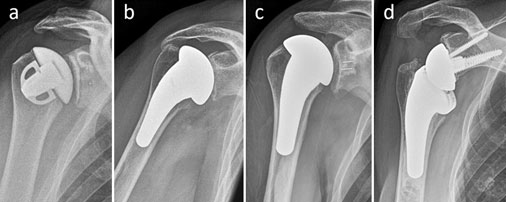

Entscheidend für den Erfolg der künstlichen Gelenke ist unter anderem, dass für jeden Patienten ein geeigneter Prothesentyp zur Verfügung steht, denn die Ausgangslage vor der Operation unterscheidet sich bei jedem Patienten.

Verschiedene Implantate in der Schulterendoprothetik: schaftfreie Totalendoprothese (a), Hemiprothese (b), konventionelle Totalendorpothese (c) und inverse Totalendoprothese (d).

In der modernen Schulterendoprothetik stehen z. B. passgenaue Oberflächenersatzprothesen (a) zur Verfügung, die bei minimalem Knochenverlust ein optimales Ergebnis garantieren. Auf diese Weise bleibt auch genügend Knochen zur Verfügung, um später einmal auf ein anderes System zu wechseln.

Patienten mit zerstörter Knochensubstanz brauchen einen Ersatz des Kopfes mit Schaftverankerung (b) und bei Zerstörung der Schulterpfanne einen zusätzlichen Pfannenersatz (c).

Bei kompletter Zerstörung von Schulterpfanne, Oberarmkopf und Schultermuskulatur wird ein Prothesentyp benötigt, der in der Lage ist, diese Defizite auszugleichen und die Funktion der Schulter wiederherzustellen (d). Dazu hat sich die sogenannte inverse Schulterprothese bewährt.